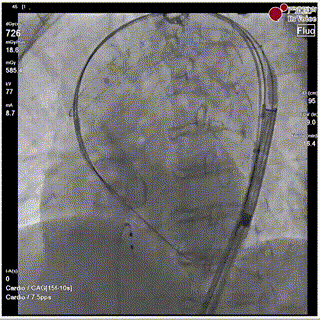

手术瓣膜释放后造影(4例)

病例一

病例二

病例三

病例四

快速过弓跨瓣(4例)